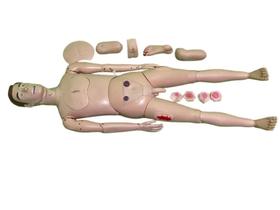

Gente, os modelos anatômicos e simuladores são cópias exatas de diferentes órgãos do corpo de humanos e dos animais, que servem pra professores e outros profissionais mostrarem como funcionam os sistemas do corpo. Eles imitam a estrutura interna e externa do organismo e também são usados pra treinamentos práticos! Quer saber mais sobre eles? Vem comigo que eu te conto:

Gente, os modelos anatômicos e simuladores são cópias exatas de diferentes órgãos do corpo de humanos e dos animais, que servem pra professores e outros profissionais mostrarem como funcionam os sistemas do corpo. Eles imitam a estrutura interna e externa do organismo e também são usados pra treinamentos práticos! Quer saber mais sobre eles? Vem comigo que eu te conto:

- Olha, os modelos anatômicos e simuladores são usados em áreas como Medicina, Enfermagem, Fisioterapia e Veterinária pra imitar órgãos como o coração, rins, útero, olhos, cérebro, as articulações e até o esqueleto inteiro.

- Esses modelos são feitos de resina ou de propiletileno, que é um plástico mais duro, e são desmontáveis, pra apontar todos os detalhes dos órgãos, como camadas, veias e nervos.

- Agora, o simulador pode imitar adultos, idosos e crianças de corpo inteiro ou apenas uma parte dele, como a perna, a cabeça, o pé ou o tronco.

- E tem modelos que vêm com recursos digitais, como programas que reproduzem situações de risco de vida e que indicam quando o procedimento está sendo feito da forma certa. Legal!

Aqui no Magazine Luiza tem vários modelos anatômicos e simuladores. Vem ver!